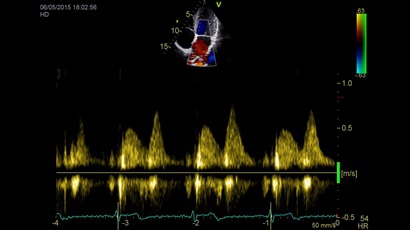

Тканевой допплер:

Да

Цветовой допплер:

Импульсно-волновой допплер:

• Режимы: 4D, 2D (B-режим), цветной допплеровский режим, режим энергетического допплера, M-режим, цветной M-режим, спектральные режимы импульсно-волнового допплера (PW) и непрерывно-волнового допплера (CW), визуализация скорости движения тканей.